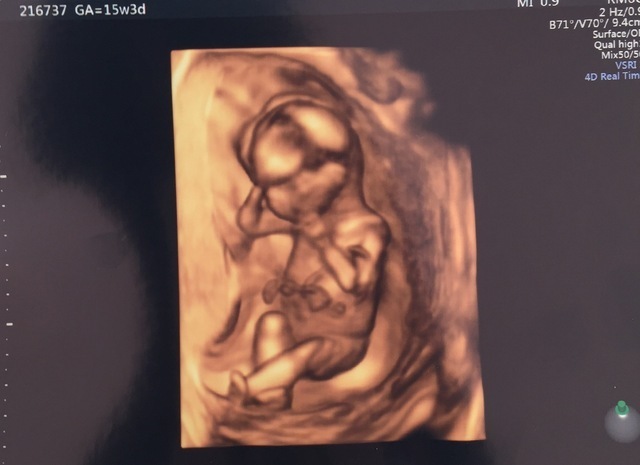

15週6日(15w6d・男の子)|ぷるぷる姫 さん(33歳)

エコー写真撮影時のエピソード:

顔が見えたとき。手で顔を触って、撫でているようで、すごく愛おしく感じました。今まで2Dの画像のみだったのが、3Dで顔の形、手の形が見え、お腹の中で育っていく様子を感じることが出来ました。

発育過程は教科書的には十分理解していますが、自分のお腹の中でその過程が進んでいるのはとても不思議な気持ちでした。